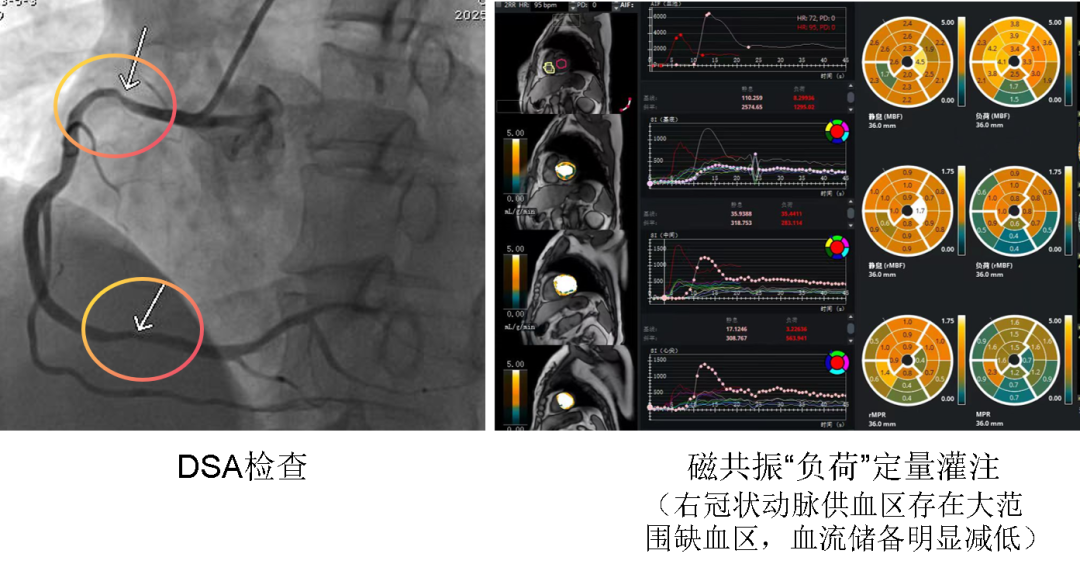

▲治療前 此次接受檢查的患者因間斷頭暈、心悸胸悶、暈厥來滄州市中心醫(yī)院就診。心臟彩超、動(dòng)態(tài)心電圖未見異常。冠脈造影提示右冠狀動(dòng)脈臨界病變,無法確定是否有心肌缺血的存在。經(jīng)心臟中心專家會(huì)診,決定采用這項(xiàng)國際領(lǐng)先技術(shù)進(jìn)行更深入的檢查。檢查過程中,專家團(tuán)隊(duì)?wèi){借豐富的經(jīng)驗(yàn)和高超的技術(shù),嚴(yán)格把控每一個(gè)環(huán)節(jié),確保檢查操作精準(zhǔn)無誤。檢查結(jié)果清晰、直觀地顯示了患者心肌缺血的具體部位和嚴(yán)重程度,不僅明確了診斷,更實(shí)現(xiàn)了對(duì)心肌缺血程度的全定量分析,為后續(xù)精準(zhǔn)治療提供了強(qiáng)有力的科學(xué)支撐。 ▲治療后 心臟中心專家憑借深厚的臨床經(jīng)驗(yàn),精準(zhǔn)把握適應(yīng)癥,為患者量身定制最優(yōu)檢查方案;磁共振成像科團(tuán)隊(duì)則依托先進(jìn)的磁共振設(shè)備和嫻熟的操作技術(shù),確保了圖像采集的高質(zhì)量與高精度。從檢查前的充分溝通、周密準(zhǔn)備,到檢查中的默契配合、無縫銜接,再到檢查后的聯(lián)合分析、精準(zhǔn)解讀,兩個(gè)團(tuán)隊(duì)以高度的專業(yè)素養(yǎng)和協(xié)作精神,為患者提供了全方位、一站式的優(yōu)質(zhì)診療服務(wù),充分彰顯了滄州市中心醫(yī)院強(qiáng)大的綜合實(shí)力。